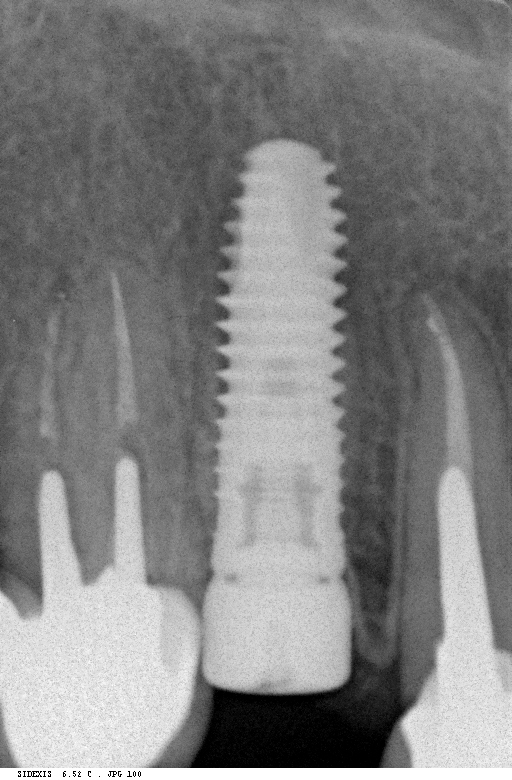

Исследование на рентгене после имплантации зубов

Раздел: Снимки-откровения